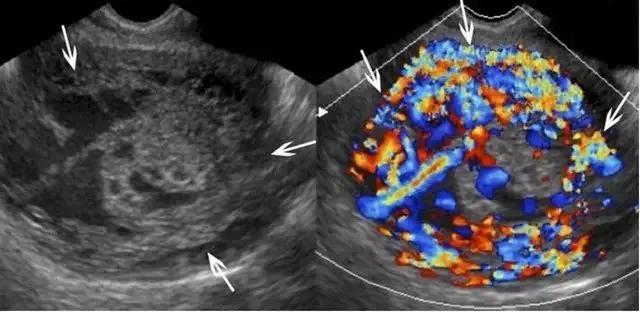

滋养层胎盘肿瘤包括一组源于胎盘滋养组织的相关肿瘤,如部分性及完全性葡萄胎、侵袭性葡萄胎、绒癌、胎盘滋养层肿瘤。引起本病的风险因素包括高龄孕妇与既往患过胎盘滋养层肿瘤病史。部分或完全性葡萄胎是良性病变,部分性葡萄胎伴有胎儿存活,而完全性葡萄胎没有胎儿,其患绒癌的风险性更大。在超声上,葡萄胎的子宫增大,部分性葡萄胎的子宫可见多个弥漫性无回声病变,胎儿因多发先天性畸形、三倍体及生长受限而不能存活(图 16)。

图 16 示部分性葡萄胎:A 为子宫横断面,箭头示宫内不均质囊实性包块,血流丰富,宫内可见积液。B 示宫内另可见部分胎儿(小箭头)及较短的脐带(长箭头、)。C 为盆腔矢状位的压脂像 T2WI,上方箭头示宫内不均质包块,下方箭头示部分胎儿

完全性葡萄胎在早孕期呈现为子宫增大、宫腔充满不均质的伴血流的高回声组织,宫内可出现小囊肿,可误认为早孕。妊娠后期时,宫内充满高回声包块,内含多个无回声囊性暗区(即水肿的绒毛),称为「瑞士奶酪」或「暴风雪」 征(图 17)。双侧卵巢可有黄素囊肿(即较大的多分隔囊肿),系 HCG 增高引起。宫内包块为高速低阻血流,与宫内正常弓状低速低阻血流不同。在双卵双胎妊娠,可同时并存葡萄胎与正常妊娠。此时,正常胎儿可有正常胎盘,这与部分性葡萄胎不同。